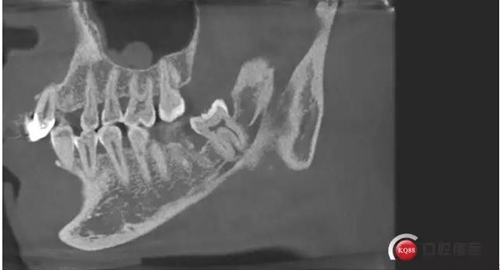

下面CBCT,可以看到兩個牙根的根尖三分之一在神經(jīng)管里面。

下面?zhèn)惹忻?/p>